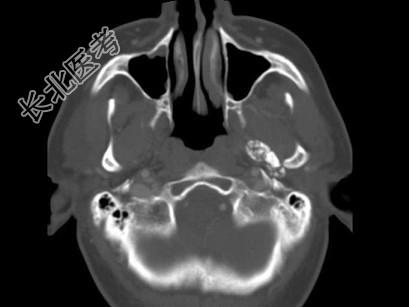

- 多项选择题男,60岁, 张口受限半年,CT检查如图所示, 正确的描述或诊断是 ( )

A、左侧颞颌关节周围软组织内见较多致密钙化影

B、左侧颞颌关节软组织未见肿胀

C、左侧颞颌关节面(颞骨面)骨质增生明显

D、左侧颞颌关节滑膜骨软骨瘤病

E、颞颌关节功能紊乱